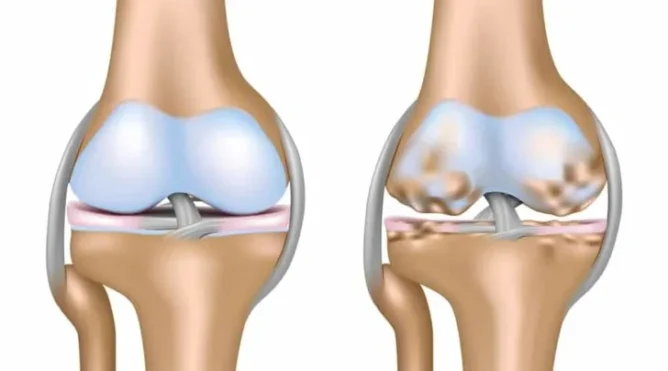

Thoái hóa khớp gối, hay còn gọi là osteoarthritis, là một tình trạng mà sụn khớp – vật liệu đệm giữa các khớp xương – bị bào mòn dần theo thời gian. Điều này khiến cho xương dưới sụn bị tổn thương, dẫn đến đau, sưng và hạn chế chuyển động. Thoái hóa khớp gối thường xảy ra do quá trình lão hóa tự nhiên, nhưng cũng có thể do yếu tố di truyền, chấn thương hoặc tải trọng quá mức từ việc thừa cân.